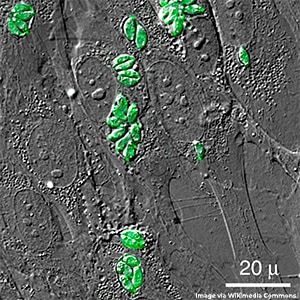

The blood-brain barrier protects the brain from harmful substances and pathogens, but it also prevents the delivery of certain drugs and other therapeutics to brain tissue, including brain tumors. The protozoan parasite Toxoplasma gondii (T. gondii) can traverse this barrier, causing an infection known as toxoplasmosis.

In a recent study in Nature Microbiology, researchers engineered these creepy crawlies to secrete proteins of interest directly into brain cells. T. gondii uses two systems to secrete proteins into host cells: the rhoptries, through which T. gondii outside the cell can push proteins through the host cell membrane, and the dense granules, through which T. gondii inside the cell can secrete proteins directly into the cytosol. By fusing proteins of interest with proteins typically secreted through each of these pathways, the researchers showed that engineered T. gondii could successfully deliver target proteins to neurons in vitro using both secretion pathways and that those fusion proteins functioned as expected in host cells. Engineered T. gondii also trafficked to the brain and delivered fusion proteins in vivo.

The researchers noted that delivering enough protein to have a therapeutic effect would likely require them to boost the secretion capabilities of T. gondii or attenuate its infectiousness so more parasites can be delivered. While more research is required, the study authors expressed hope that these microscopic brain-dwellers can someday deliver therapeutics.